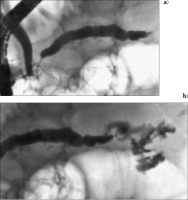

Abbildung 2: a) Die ERCP vom 15.3.2004 zeigt via die große Papille das normale Gallengangsystem und den Ductus Wirsungianus. b) Über die Minorpapille (→) wurde der im Kopfbereich schmale Ductus Santorini und der im Korpus leicht dilatierte Pankreashauptgang angespritzt. Im Bereich des Kopfes besteht eine leichte Kompression des Hauptganges (←).

Keywords: chronische PankreatitisERCPGastroenterologie

Abbildung 3: a) Die ERCP vom 13.7.2005 zeigt via die Minorpapille die mittlerweile deutlichere Einengung des Ductus Santorini im Bereich des Pankreaskopfes und den konsekutiven Gangaufstau des Hauptganges (Ductus Wirsungianus). b) Bei weiterem Anspritzen des Ganges tritt Kontrastmittel in die später intraoperativ als nekrosehaltig identifizierte Pseudozyste über.